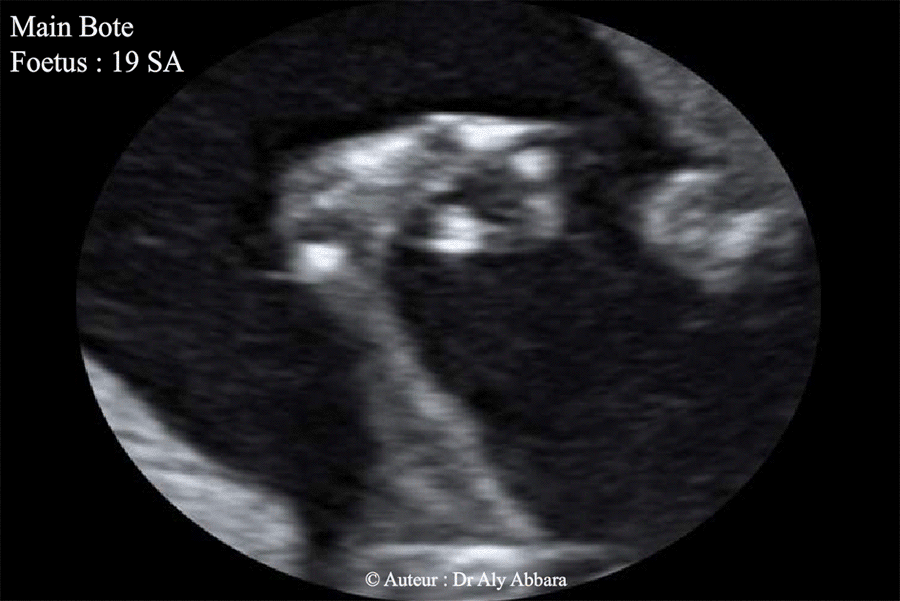

Mains botes - foetus de 19 SA - Trisomie 18

Main bote faisant partie d'un syndrome polymarformatif : Trisomie 18

Fœtus âgé de 19 SA.

On observe aussi que le majeur et l'annulaire sont plus fléchis que l'index et l'auriculaire, avec la flexion accentuée du pouce vers la face palmaire de la main ; il s'agit d'une forme mineure de la main crispée ; signe retrouvé dans 50 % des cas de trisomie 18.

Main bote :

(main émoussée, arrondie : la main est repliée en permanence sur l'avant-bras donne à l'extrémité de ce dernier un aspect arrondi).

Il s'agit d'une anomalie congénitale du positionnement et de l'attitude de la main sur l'avant-bras.